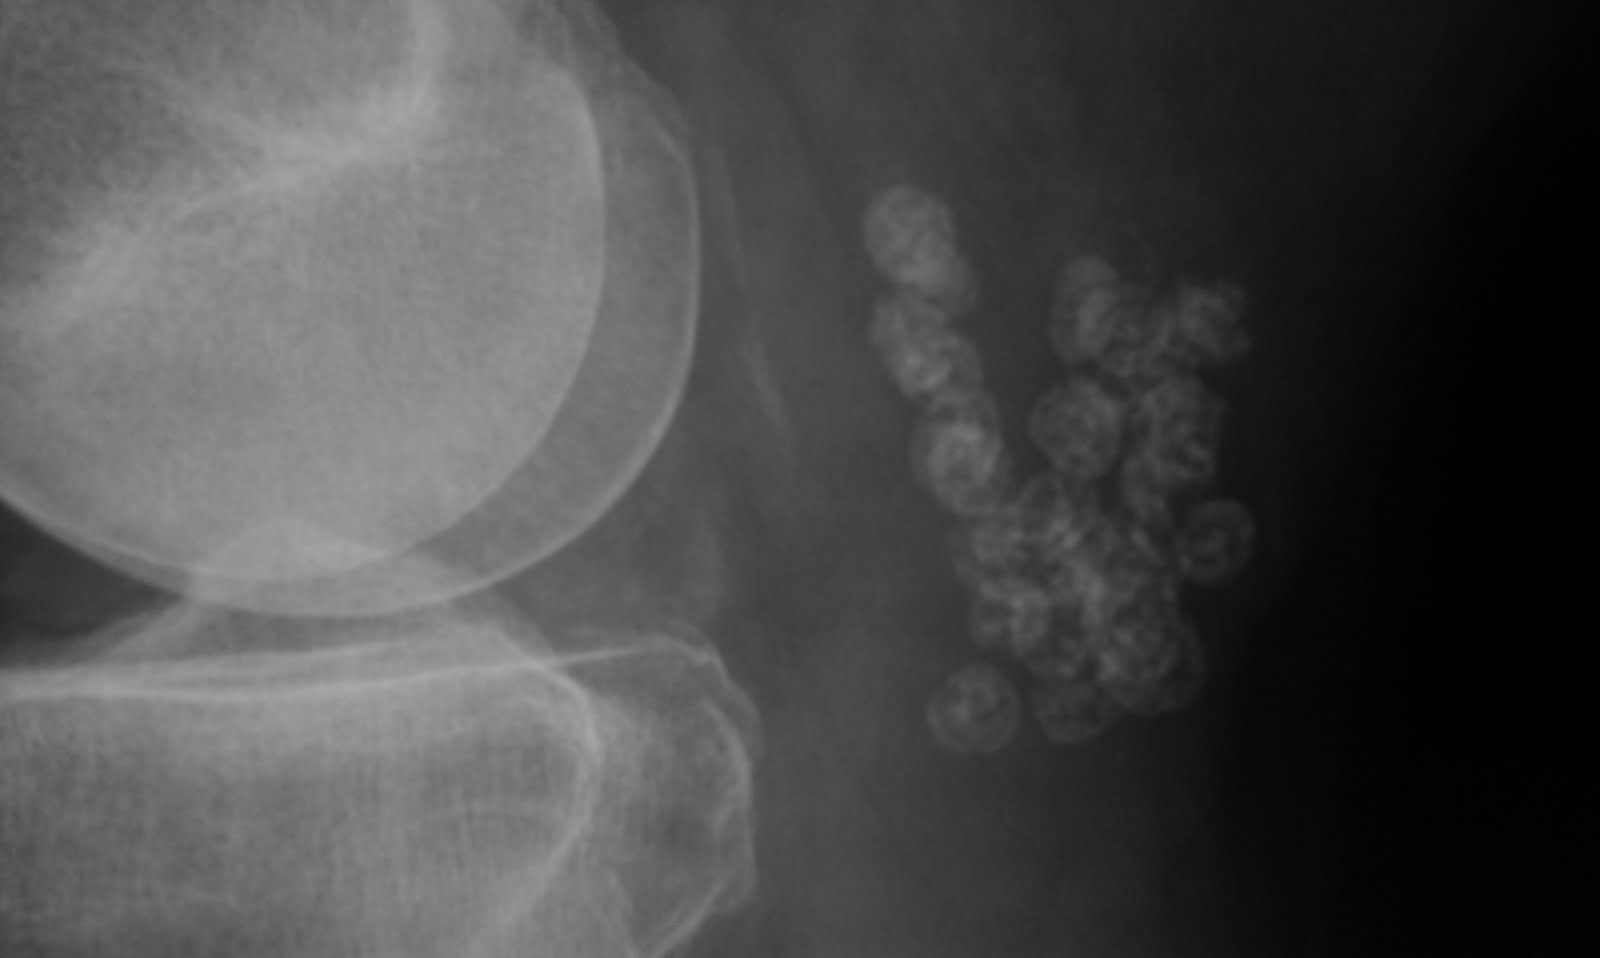

From radiologyimages.blogspot.com

Daily Dose ? Synovial osteochondromatosis of Baker's cyst Baker's Cyst Show Up On Xray learn about the causes, symptoms, diagnosis, and treatment of popliteal cysts, also known as baker's. Learn how to diagnose it with. It can be caused by knee injuries or. learn about the causes, symptoms, and diagnosis of baker cysts, also known as popliteal cysts, which are. Learn about the diagnosis and treatment options for this condition. It can. Baker's Cyst Show Up On Xray.

From journals.lww.com

Baker Cyst Calcifications in a Patient With Rheumatoid Arthr... JCR Baker's Cyst Show Up On Xray Learn how to diagnose it with. learn about the causes, symptoms, and diagnosis of baker cysts, also known as popliteal cysts, which are. It can result from a problem inside the knee joint, such as osteoarthritis or a meniscus tear. It can be caused by knee injuries or. Learn about the diagnosis and treatment options for this condition. . Baker's Cyst Show Up On Xray.